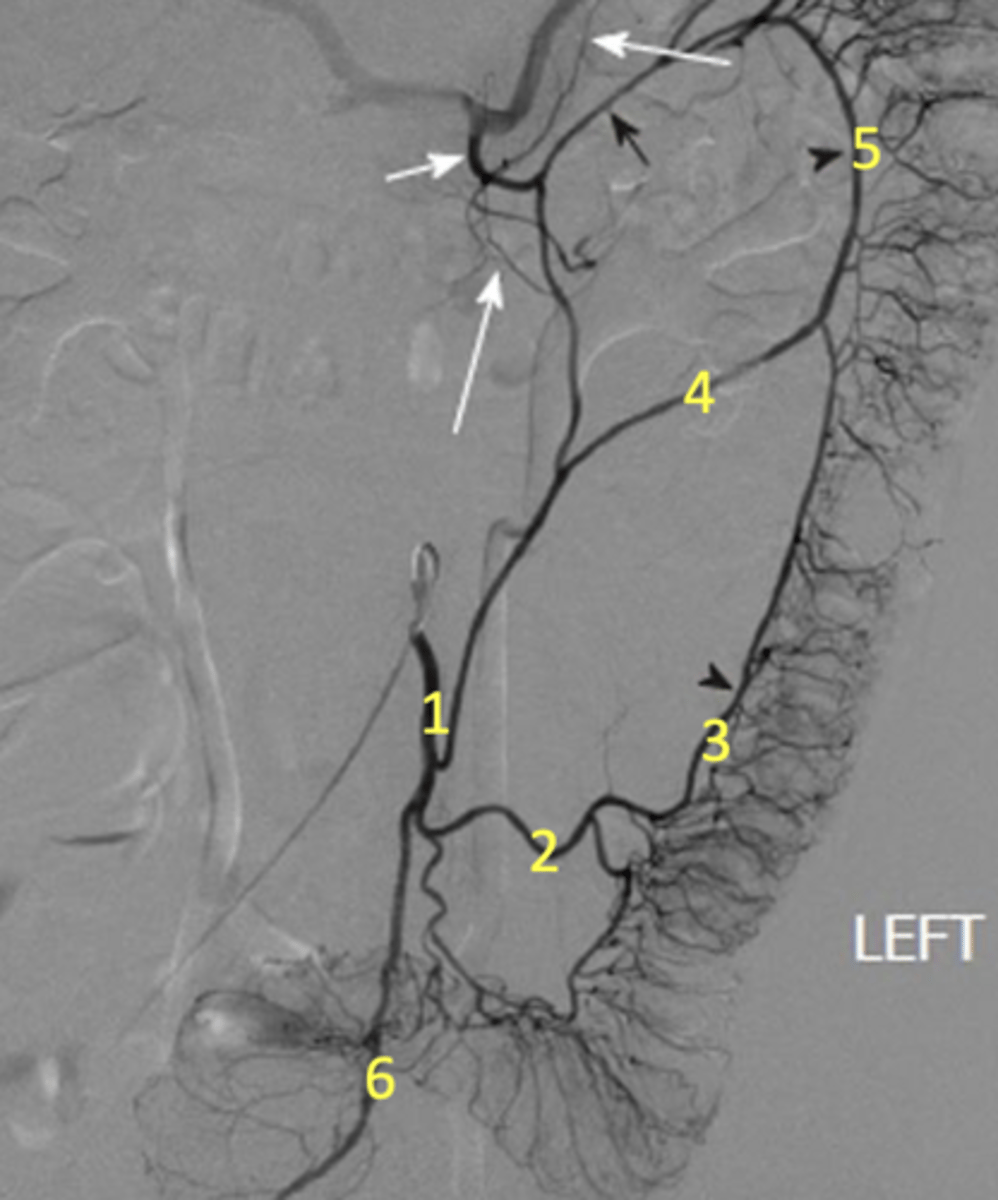

1. Inf. mesenteric a

2. sigmoidal a

3. marginal a

4. left colic a

5. marginal a again

6. superior rectal a

Label the radiograph